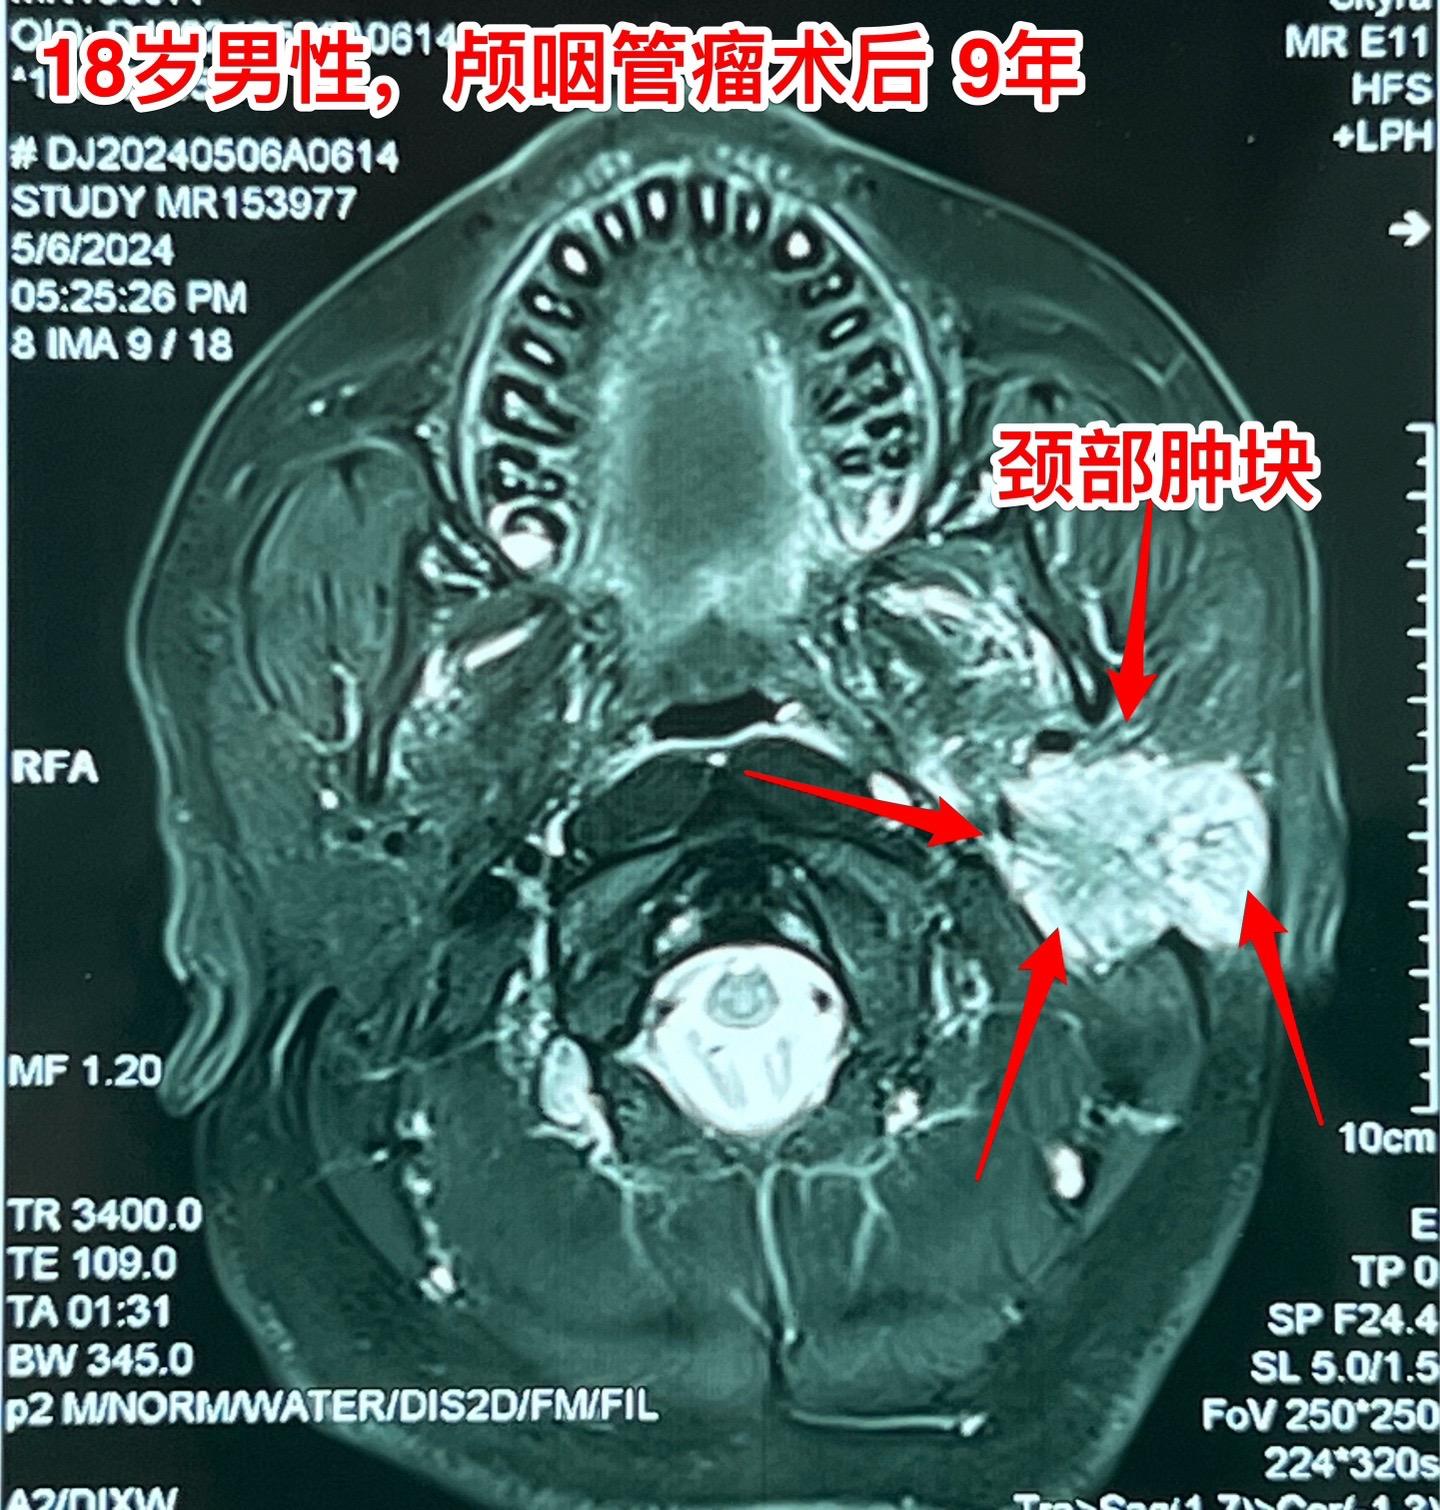

颅咽管瘤手术后9年,左侧颈部出现肿块。这周,一个来自焦作市的18岁年轻人来三博脑科医院复查,他在2015年在我这里作了颅咽管瘤切除手术,这些年多次复查磁共振都没有发现颅咽管瘤复发。 但是近期他的左侧耳朵下方颈部出现肿块,见图。在外院做了肿块穿刺活检,病理报告见图,报告怀疑是“粘液表皮样癌”。病人和家长来找我,目的是让我来判断这个颈部肿块是不是颅咽管瘤转移到颈部的? 我仔细看了最近的磁共振,原来的颅咽管瘤没有复发!而现在的颈部肿块是另一个肿瘤!不是颅咽管瘤! 家长又